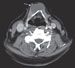

A 69-year-old man with stage II chronic kidney disease due to hypertension fell from his bicycle and presented to the emergency department (ED) with abrasions, ecchymoses, and a 3-cm laceration on his right leg. The patient was an avid cyclist. His wounds were cleaned and the laceration sutured. There were no fractures, and the patient was discharged home.